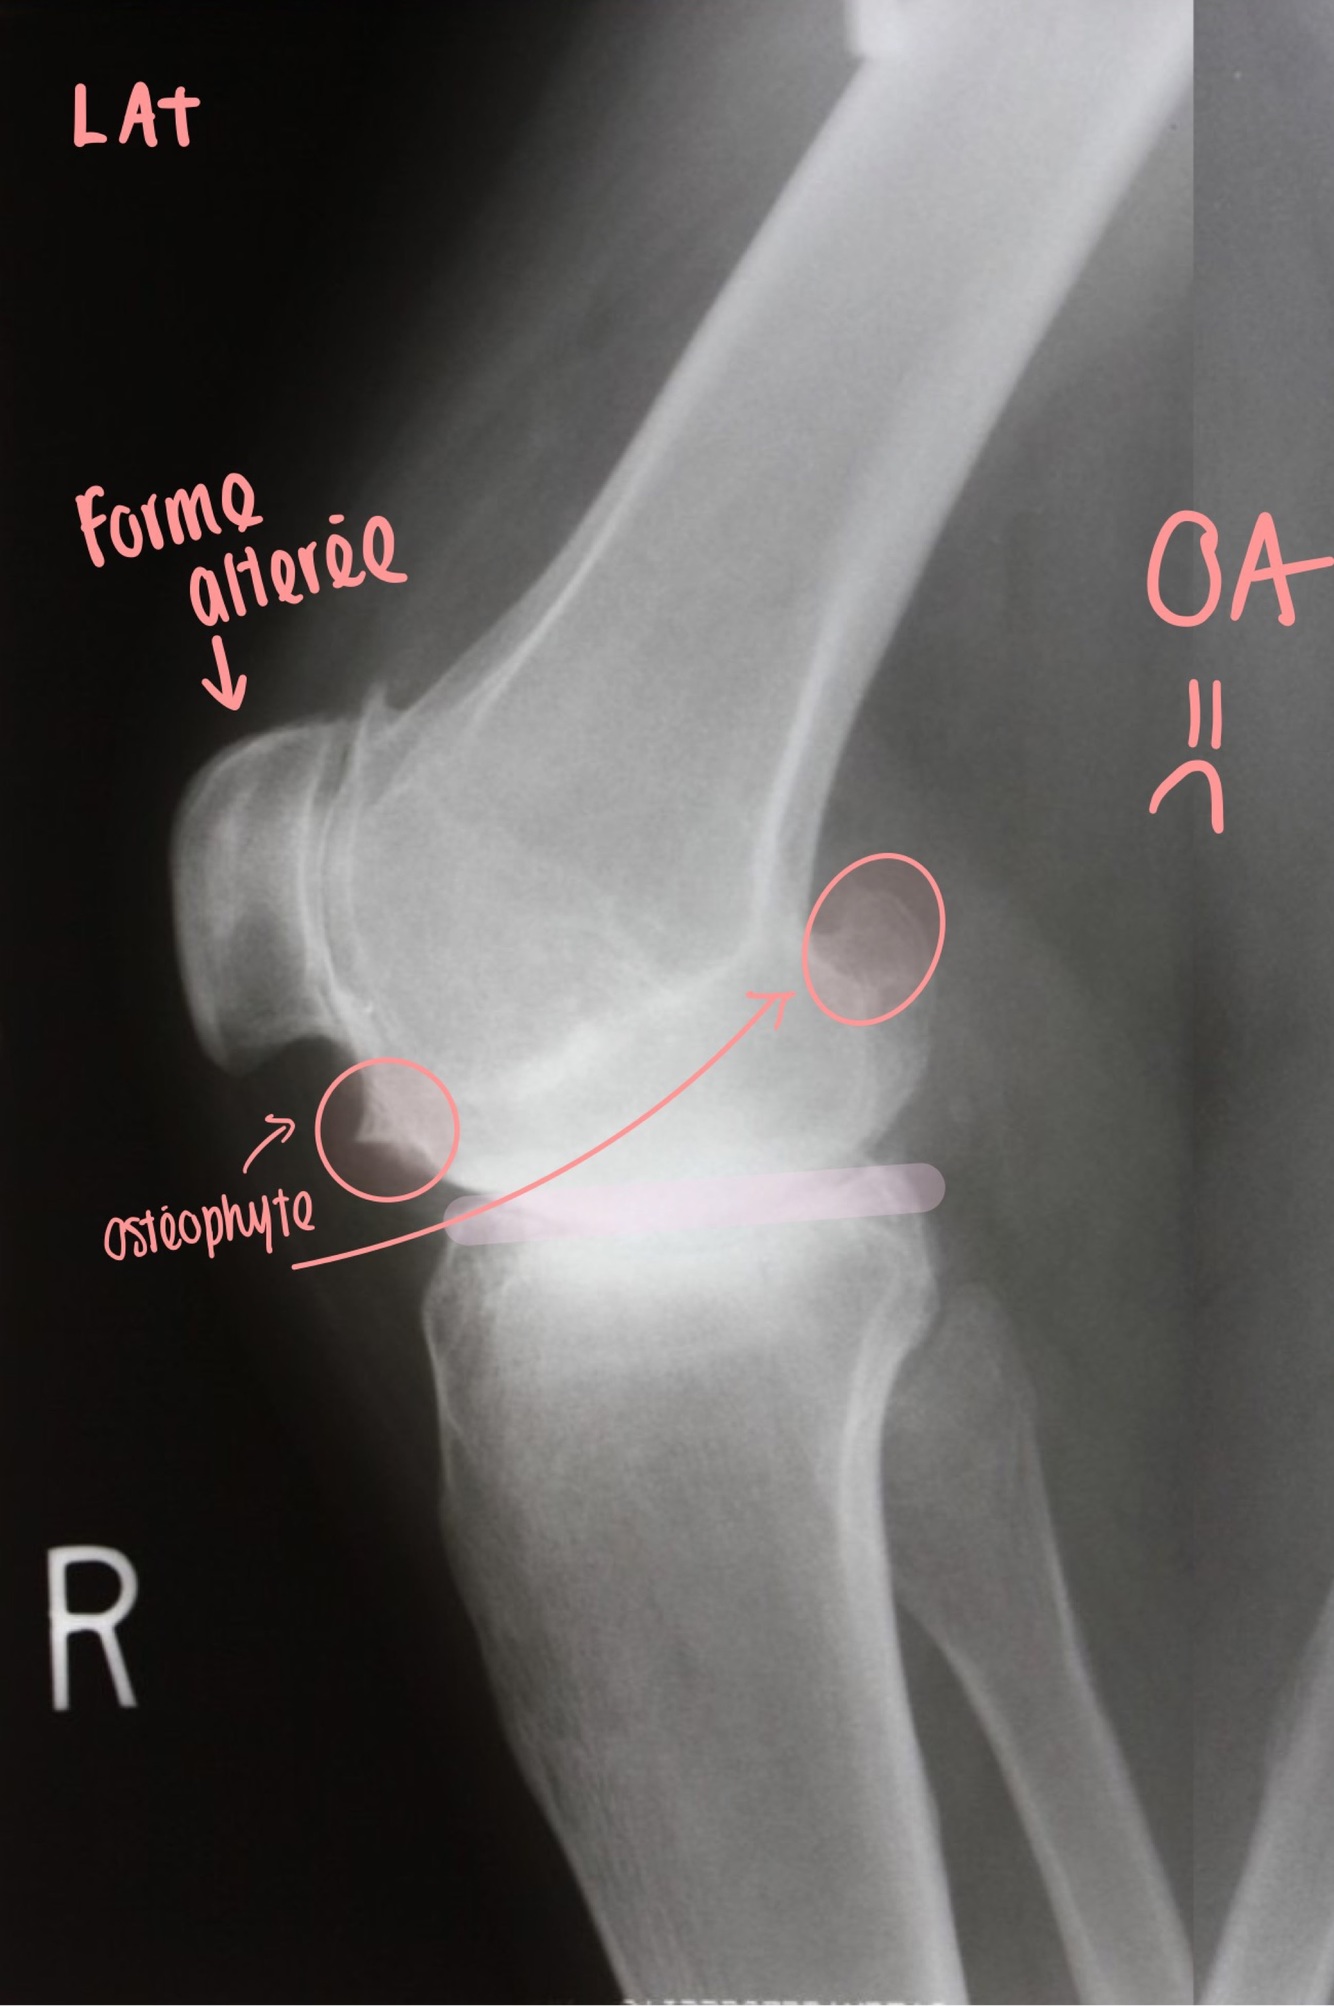

Q

Dx?

A

How well did you know this?